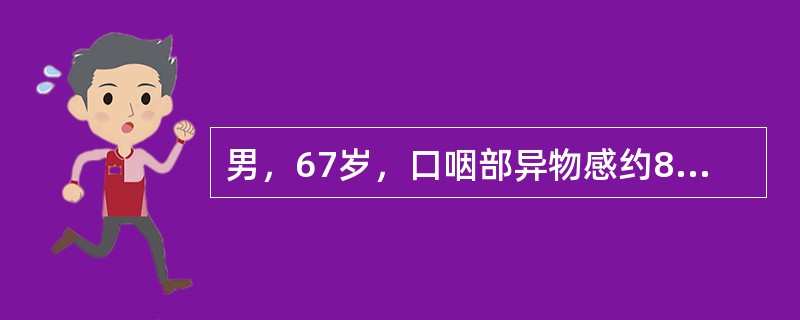

男,67岁,口咽部异物感约8个月,伴口咽部疼痛,患者无明显发热。如图所示最可能的诊断为()

男,67岁,口咽部异物感约8个月,伴口咽部疼痛,患者无明显发热,影像检查如图,最可能的诊断是<img border="0" style="width: 294px;

[单选题]男,67岁,口咽部异物感约8个月,伴口咽部疼痛,患者无明显发热,影像检查如图,最可能的诊断是A.扁桃体结核伴淋巴结转移B.扁桃体脓肿伴淋巴结转移C.扁

男,67岁,口咽部异物感约8个月,伴口咽部疼痛,患者无明显发热,影像检查如图,最可能的诊断是<img border="0" style="width: 297px;

[单选题]男,67岁,口咽部异物感约8个月,伴口咽部疼痛,患者无明显发热,影像检查如图,最可能的诊断是A.扁桃体结核伴淋巴结转移B.扁桃体脓肿伴淋巴结转移C.扁

男,67岁,口咽部异物感约8个月,伴口咽部疼痛,患者无明显发热,影像检查如图,最可能的诊断是()<img border="0" style="width: 224p

[单选题]男,67岁,口咽部异物感约8个月,伴口咽部疼痛,患者无明显发热,影像检查如图,最可能的诊断是()A.扁桃体结核伴淋巴结转移B.扁桃体脓肿伴淋巴结转移C

男,67岁,口咽部异物感约8个月,伴口咽部疼痛,患者无明显发热,影像检查如图,最可能的诊断是( )。<br /><img border="0" style=&q

[单选题]男,67岁,口咽部异物感约8个月,伴口咽部疼痛,患者无明显发热,影像检查如图,最可能的诊断是( )。A.扁桃体结核伴淋巴结转移B.扁桃体脓肿伴淋巴结

男,67岁,口咽部异物感约8个月,伴口咽部疼痛,患者无明显发热。如图所示最可能的

[单选题,A1型题] 男,67岁,口咽部异物感约8个月,伴口咽部疼痛,患者无明显发热。如图所示最可能的诊断为()A . 扁桃体结核伴淋巴结转移B . 扁桃体脓肿伴淋巴结转移C . 扁桃体癌伴淋巴结转移D . 扁桃体淋巴瘤E . 下咽癌伴淋巴结转移

男,67岁,口咽部异物感约8个月,伴口咽部疼痛,患者无明显发热.如图所示最可能的

[单选题]男,67岁,口咽部异物感约8个月,伴口咽部疼痛,患者无明显发热.如图所示最可能的诊断为()A .扁桃体结核伴淋巴结转移B .扁桃体脓肿伴淋巴结转移C .扁桃体癌伴淋巴结转移D .扁桃体淋巴瘤E .下咽癌伴淋巴结转移

男,67岁,口咽部异物感约8个月,伴口咽部疼痛,患者无明显发热。最可能的诊断为(

[单选题]男,67岁,口咽部异物感约8个月,伴口咽部疼痛,患者无明显发热。最可能的诊断为()A . 扁桃体结核伴淋巴结转移B . 扁桃体脓肿伴淋巴结转移C . 扁桃体癌伴淋巴结转移D . 扁桃体淋巴瘤E . 下咽癌伴淋巴结转移

男,67岁,口咽部异物感约8个月,伴口咽部疼痛,患者无明显发热,影像检查如图,最

[单选题]男,67岁,口咽部异物感约8个月,伴口咽部疼痛,患者无明显发热,影像检查如图,最可能的诊断是()A . 扁桃体结核伴淋巴结转移B . 扁桃体脓肿伴淋巴结转移C . 扁桃体癌伴淋巴结转移D . 扁桃体淋巴瘤E . 下咽癌伴淋巴结转移